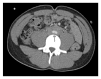

Retroperitoneal fibrosis (RPF) is a condition characterized by chronic inflammatory and fibrotic changes in the retroperitoneum that can lead to serious complications including kidney failure, mesenteric and limb ischemia, and deep venous thrombosis among others. Affected individuals may present with nonspecific symptomology that would require a high clinical index of suspicion for prompt diagnosis. We herein discuss a case of a young African-American man with recurrent deep venous thrombosis who presents with a 4-week history of constant aching pain of abdomen and back and kidney failure. Initial noncontrast computed tomogram (CT) only revealed mild bilateral hydroureteronephrosis with inflammatory changes but without obvious mass or lymphadenopathy. At the insistence of the renal consulting team to rule out RPF, a CT-urogram was performed which revealed an infiltrative mass encasing the aorta, inferior vena cava, and common iliac vessels. Laparoscopic biopsy revealed dense fibroadipose tissue, lymphocytic aggregates, focal scattered IgG4-positive plasma cells, and fibrin deposition. Patient underwent bilateral nephrostomy placement and empirical corticosteroid therapy with resolution of kidney failure. Our case illustrates a classic presentation of RPF with relatively benign findings on noncontrast CT that could have been missed if clinicians did not keep a high index of suspicion for the condition.